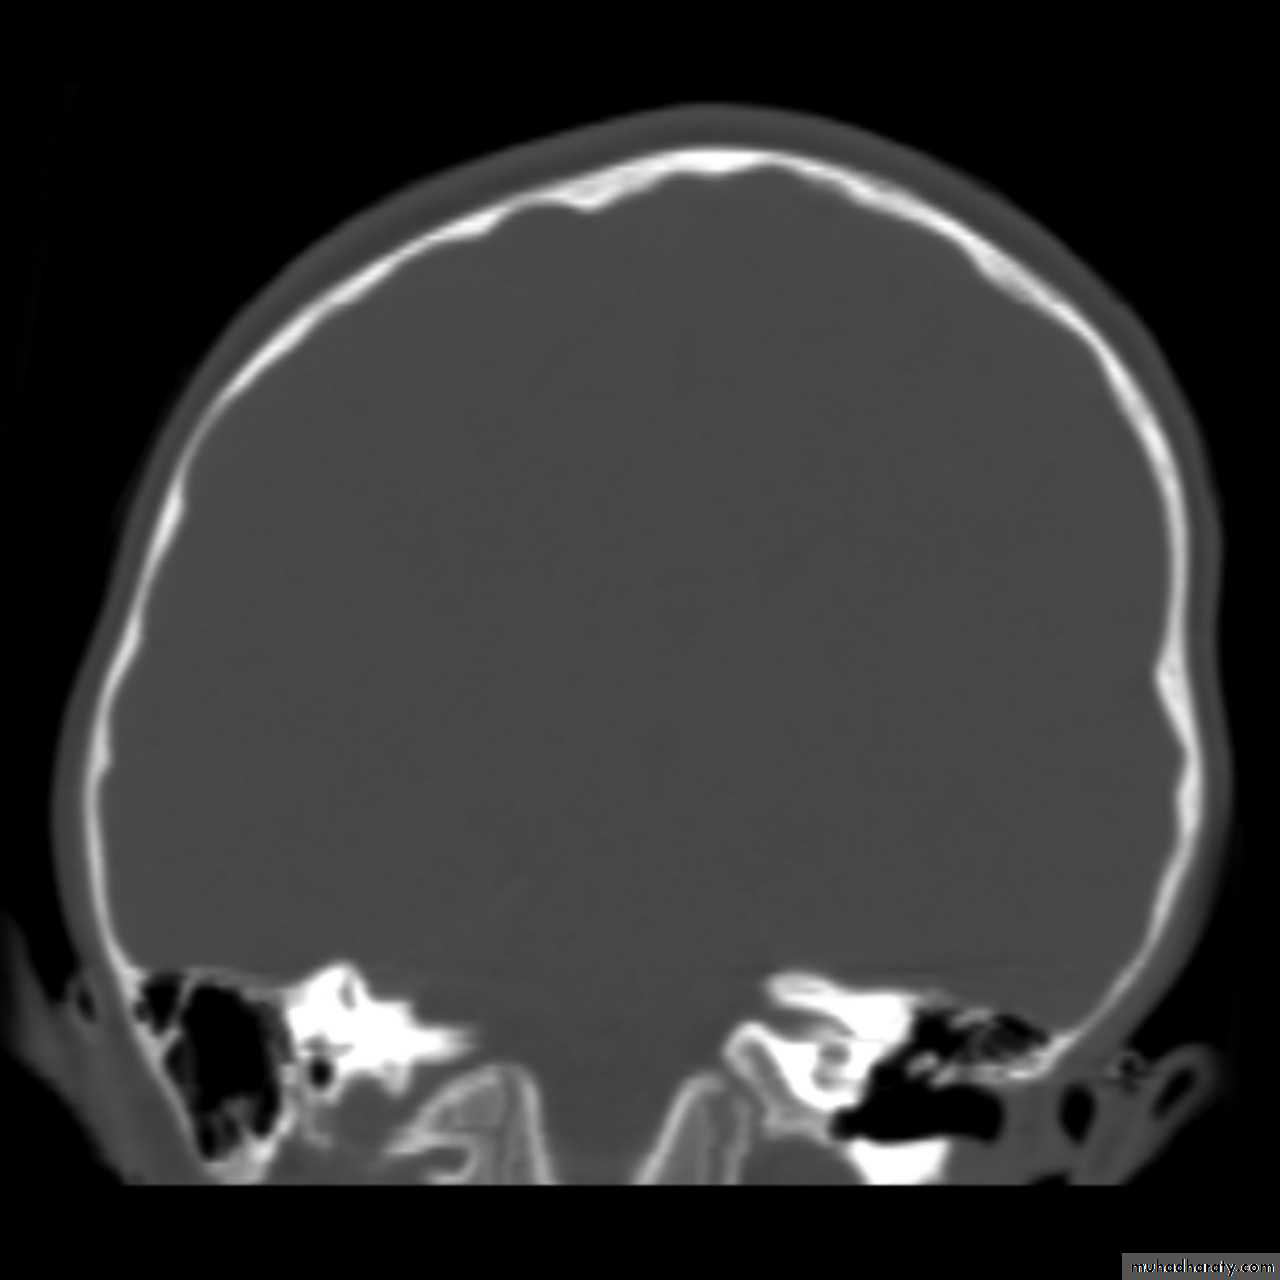

Skull X-ray findings in increased intracranial pressure

• Sutural separation in children.

• ‘Copper-beating’ marking of the cranial vault.

• Thinning of dorsum sellae.

• Erosion of the posterior clinoid process.

Copper-beating’ marking

Neurosurgery